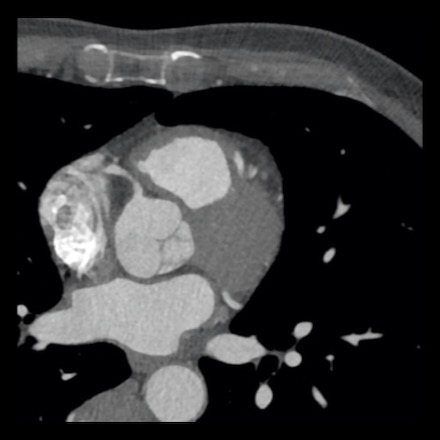

case 4 – CAD-RADS 3/P1/I+ thrombus left ventricle

First, scroll through the CTA images.

How would you describe the findings on the coronary CTA?

The findings are:

- Moderate (50-69%)

stenosis in the proximal LAD caused by a non-calcified plaque. - Variant of

sinoatrial (SA) nodal artery. The artery usually arises from the RCA as a second

branch after the conus artery, however in this case it arises from the LCX,

courses behind the aorta, anastomosing with the right atrium and with a small

branch supplies the SA-node of the heart. - Thrombus in the

apex of the left ventricle. - CTP was performed

in this patient. CTP showed a perfusion defect at stress imaging in the

territory of the LAD (I+), at rest no perfusion defect was visible.

This patient classifies as CAD-RADS 3/P1/I+, which means

this patient requires further investigation.